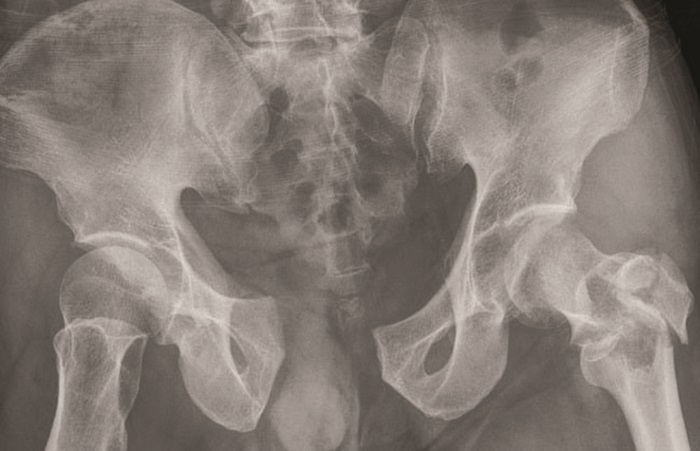

Citra Radiografi Penderita Fraktur Pelvis

Dalam kasus ini, terlihat pada citra nampak adanya kelainan pada citra pelvis pada area symphysis pubis yang terlihat terbelah.

Symphysis pubis merupakan sendi yang berada di tengah-tengah tulang panggul dan menghubungkan kedua tulang panggul.

Selain itu, adanya fraktur di femur pada bagian trochanter mayor yang mengalami keretakan.

Adapun bagian yang mengalami fraktur selanjutnya, yaitu pada bagian sacroiliac joint yang jika dilihat pada contoh gambar terdapat adanya retakan yang terbuka.

Pada contoh kasus kali ini dapat dikatakan bahwa fraktur pelvis tersebut termasuk kedalam unstable pelvic fracture yang jika dilihat dari cirinya yaitu terdapat fraktur pada anterior dan posterior pelvis. (*)